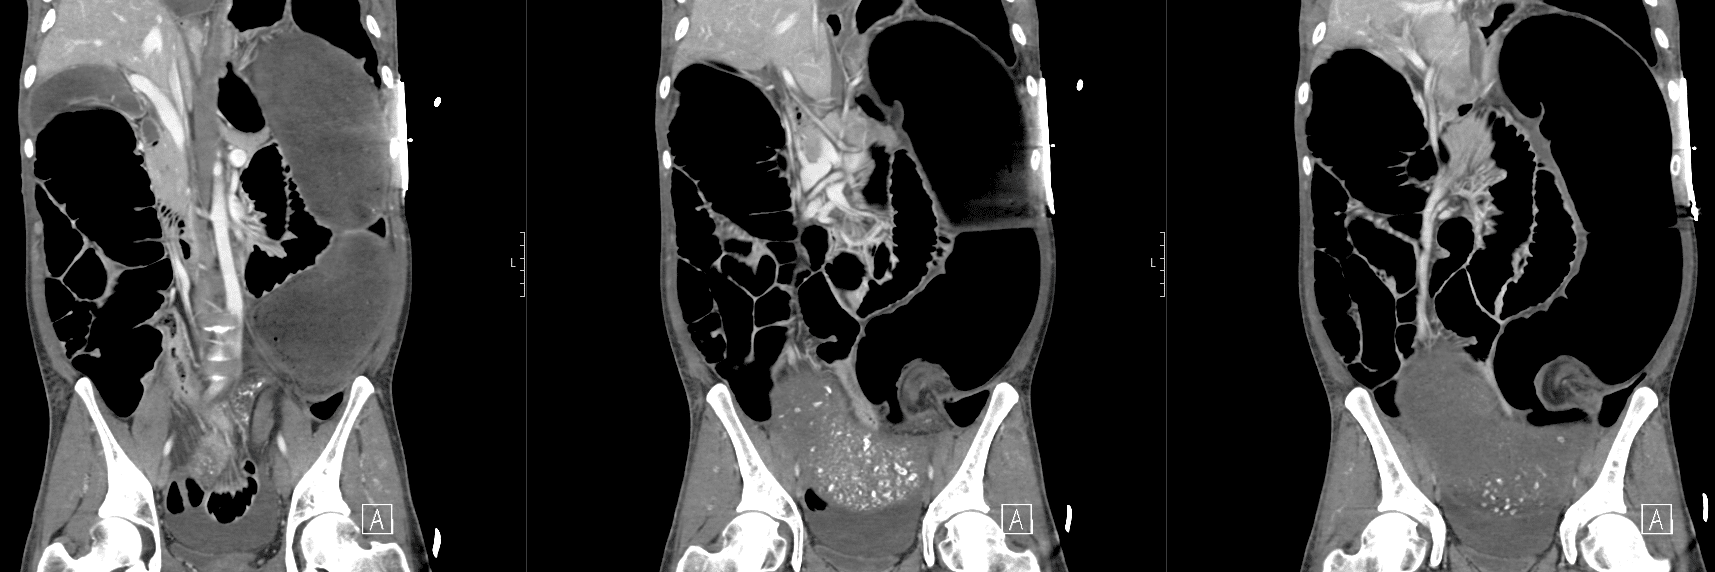

CT mesenteric angiogram

There is evidence of a sigmoid volvulus.

The proximal large bowel as well as small bowel loops are dilated suggestive of an incompetent ileocaecal valve.

There is no pneumoperitoneum to suggest hollow viscus perforation.

There is a moderate volume of free fluid. No collection.

The distended bowel compresses the liver and displaces the gallbladder and spleen posteriorly.

The abdominal aorta as well as the origins of the common iliac arteries and external iliac arteries are compressed by dilated bowel loops however remain patent and there is satisfactory flow distally to the common femoral and superficial femoral arteries.

There is narrowing of the proximal coeliac trunk likely due to compression by the median arcuate ligament. The coeliac trunk and its major branches are otherwise patent. The SMA and IMA are patent.

The distal oesophagus is distended.

The visualised lung bases are clear. No pleural effusions.

Comment: Acute sigmoid volvulus with severe bowel obstruction. The dilated bowel loops are significantly compressing the abdominal aorta and pelvic arteries as above. Urgent surgical review recommended.